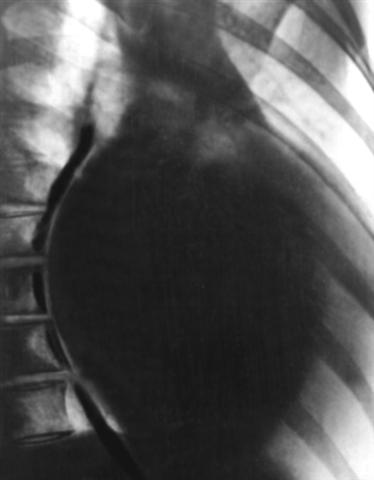

Рис. 5б). Рентгенограмма грудной клетки больной с хронической митральной недостаточностью (правое косое положение): тень сердца значительно увеличена, контрастированный пищевод отклонен кзади по дуге большого радиуса, легочный конус правого желудочка выбухает умеренно. |